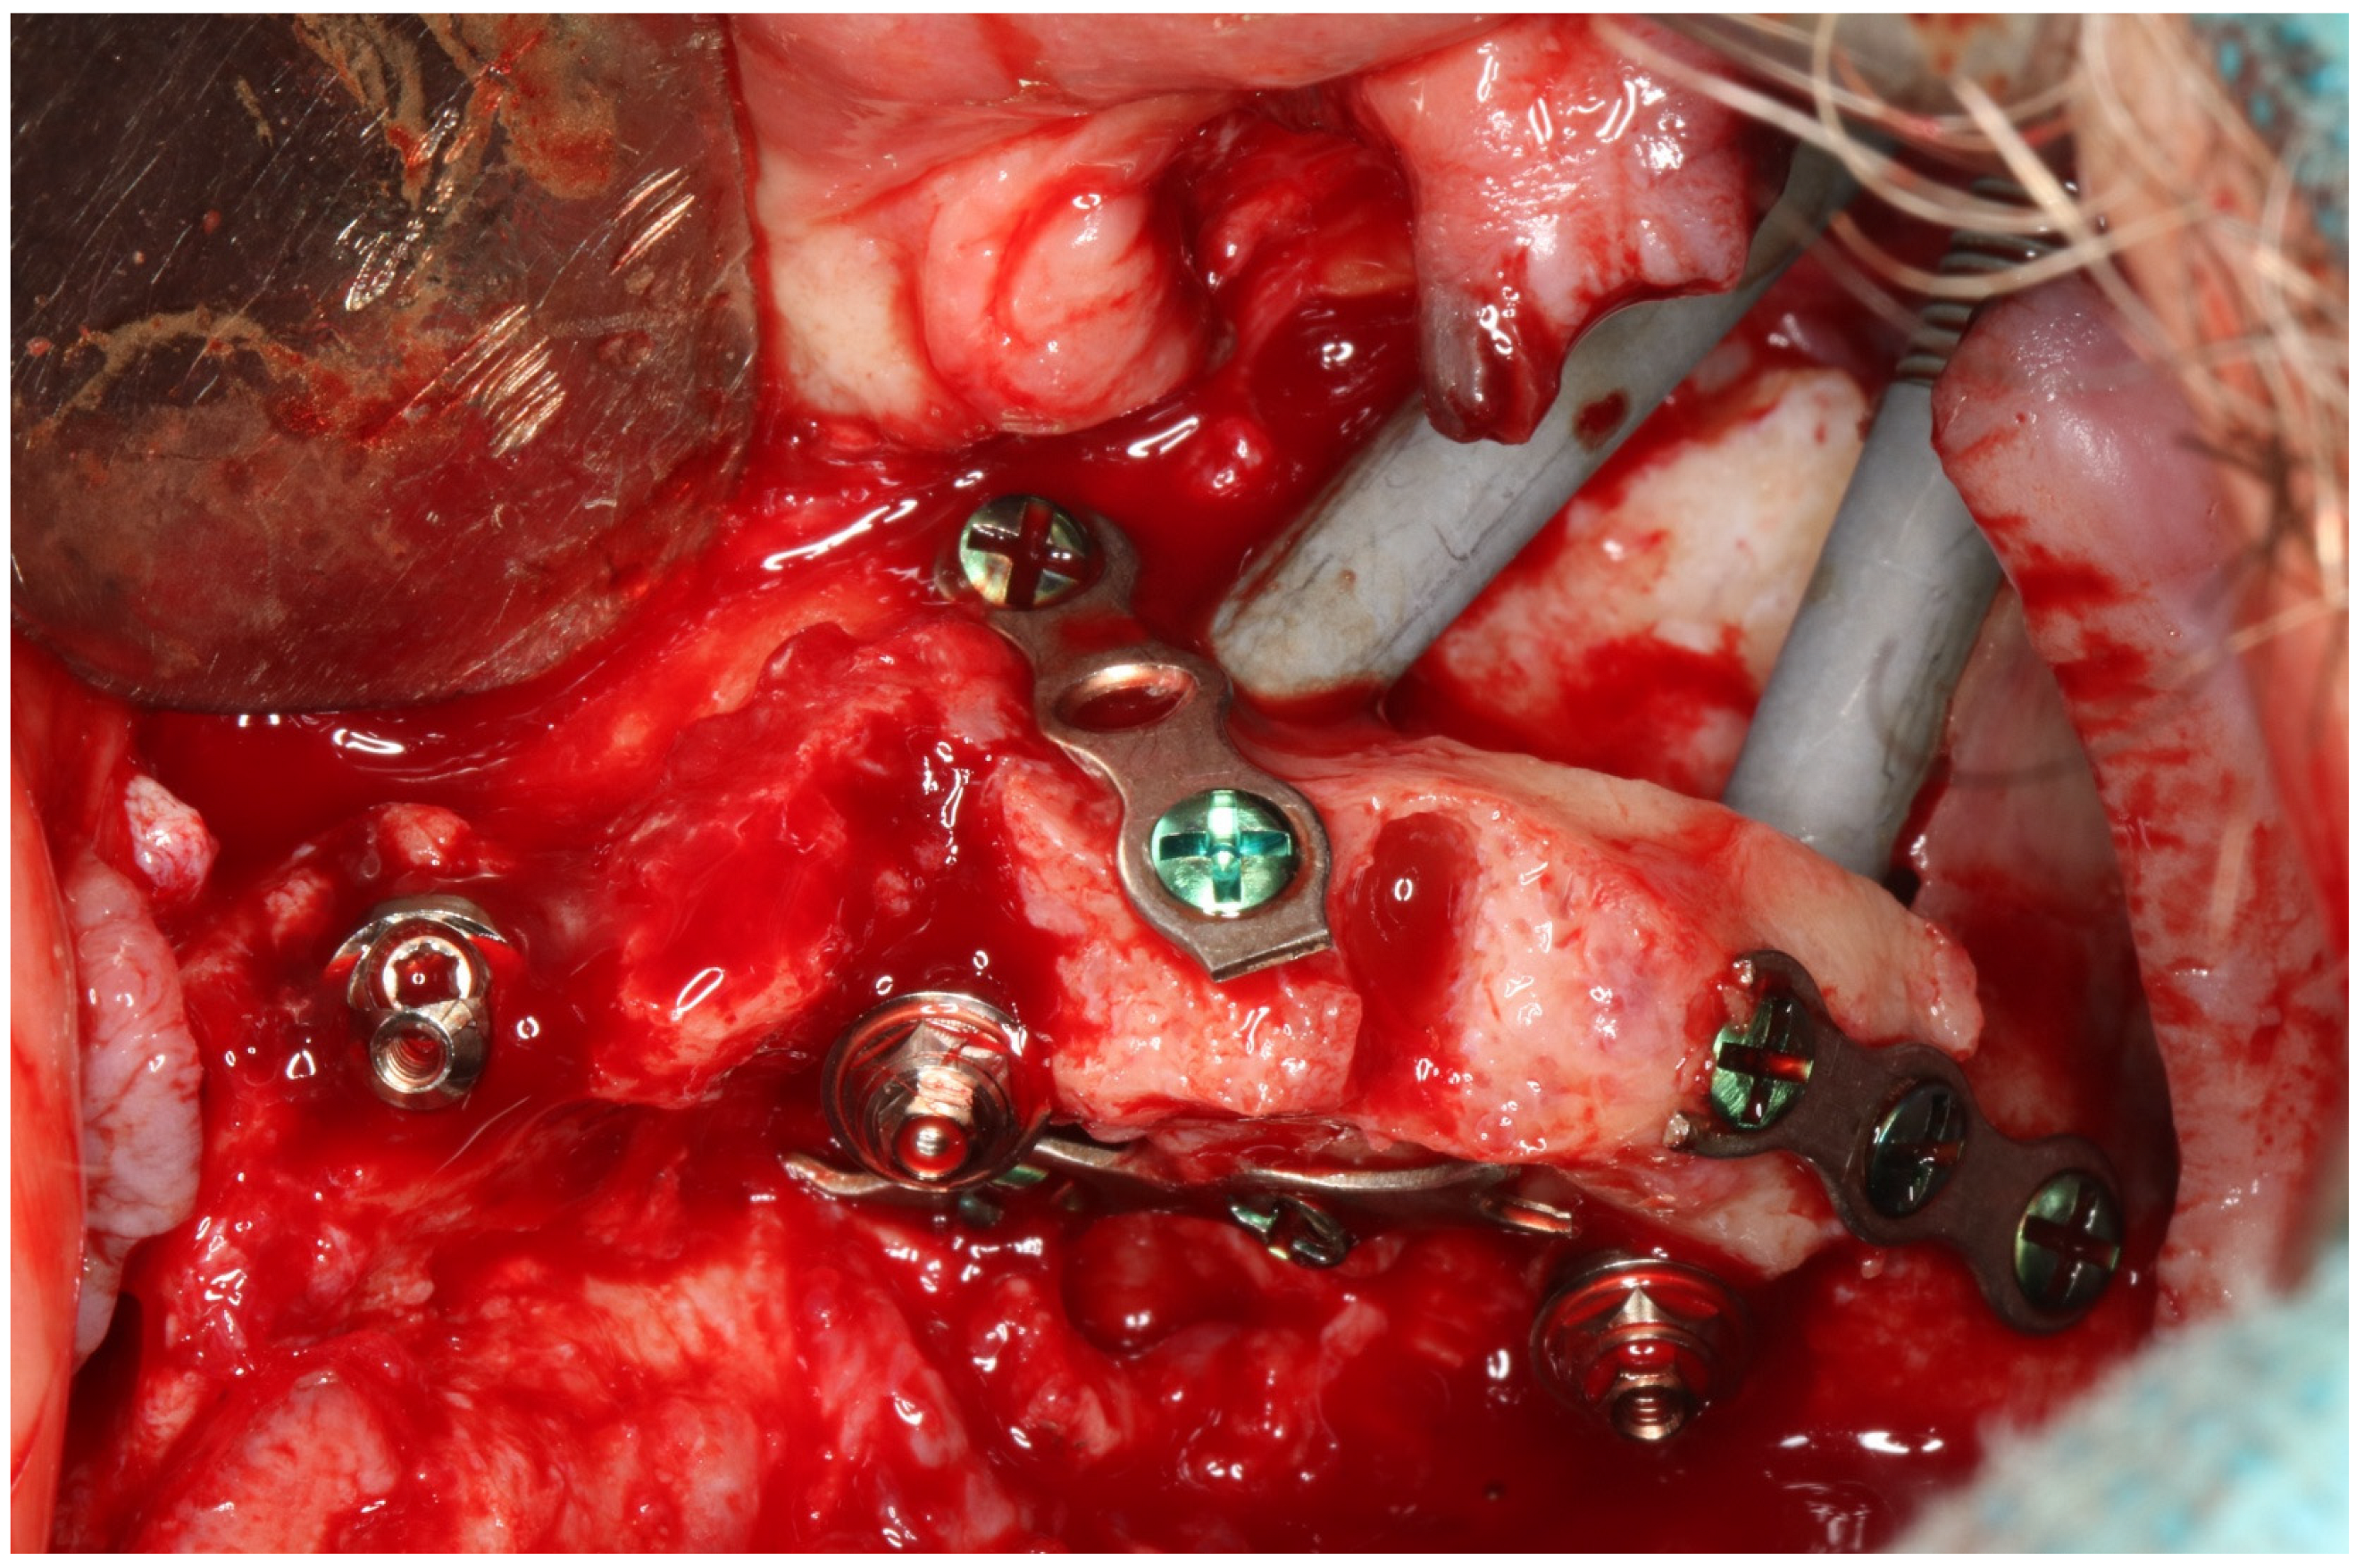

2. Materials and Methods

2.2. Surgery